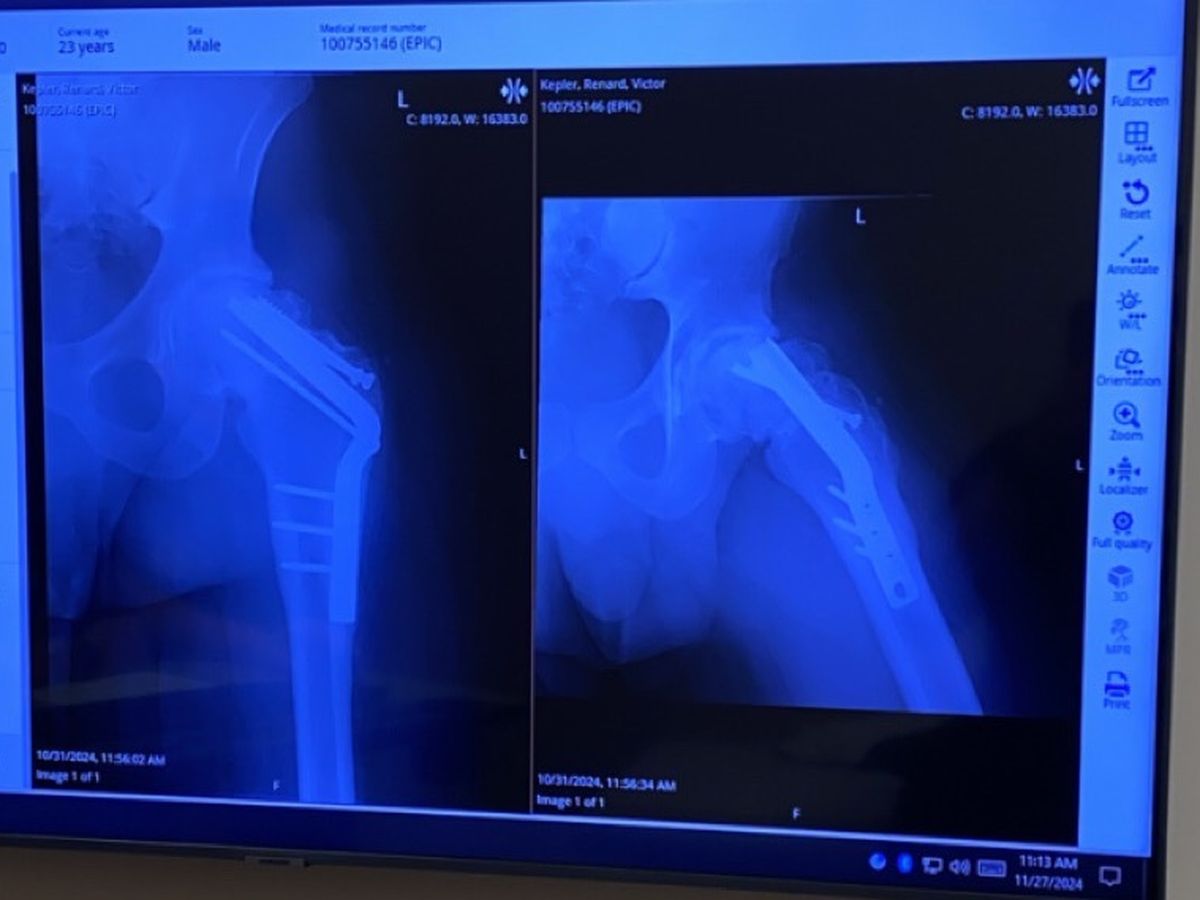

I’m reaching out because I’ve recently undergone my 4th hip surgery since being injured from being jumped back in middle school in 2013. Unfortunately, I’ve been unable to walk without assistance or work for over a month now, and my savings have been completely exhausted and I quite possibly may have to undergo a 5th surgery as well.Sadly, government assistance has not been available to me for some reason, and I’m struggling to make ends meet.